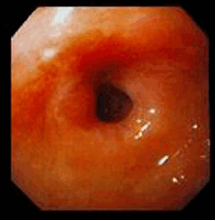

Рис.8. Эндофото. Постъязвенный рубец ДПК

III – стадия рубцевания – язва приобретает щелевидную форму с небольшой инфильтрацией и гиперемией вокруг нее; на слизистой оболочке в отдалении от язвы могут быть участки незначительной гиперемии, отека и единичных эрозий.

IV – стадия рубца Постъязвенный рубец имеет вид гиперемированного участка слизистой оболочки с линейным или звездчатым втяжением стенки (стадия «красного» рубца). В дальнейшем при эндоскопическом исследовании на месте бывшей язвы определяются различные нарушения рельефа слизистой оболочки: деформации, рубцы, сужения. Чаще всего образуются линейные и звездчатые рубцы. При заживлении глубоких хронических язв или при частых рецидивах могут развиваться грубые деформации органа и стенозы (рис. 8). Нередко заживление хронической язвы может проходить без образования видимого рубца. Зрелый рубец приобретает белесоватый вид вследствие замещения грануляционной ткани соединительной тканью и отсутствия активного воспаления (стадия «белого» рубца). Рубцы и деформация стенки желудка и ДПК, образующиеся в результате частых обострений хронических язв, служат достоверными эндоскопическими критериями ЯБ.

Результаты собственных исследований показывают, что эндоскопический метод позволяет осуществлять динамическое наблюдение за процессом рубцевания язвенного дефекта. В среднем заживление язвы желудка до образования «красного» рубца происходит за 6-7 недель, а дуоденальной язвы за 3-4 недели. Формирование полноценного рубца обычно заканчивается через 2-3 месяца (фаза «белого» рубца). Следует учитывать, что острые поверхностные язвы могут заживать в течение 7-14 дней без образования видимого рубца.